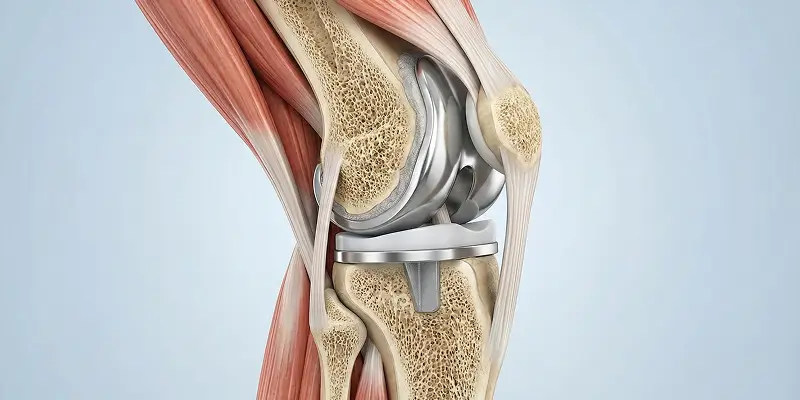

Total diz protezi, ileri osteoartrit ve diz hasarında hasarlı kıkırdak ve kemik yüzeylerinin metal ve polietilen protezle değiştirilmesidir. Endikasyonlar, cerrahi ve rehabilitasyon.